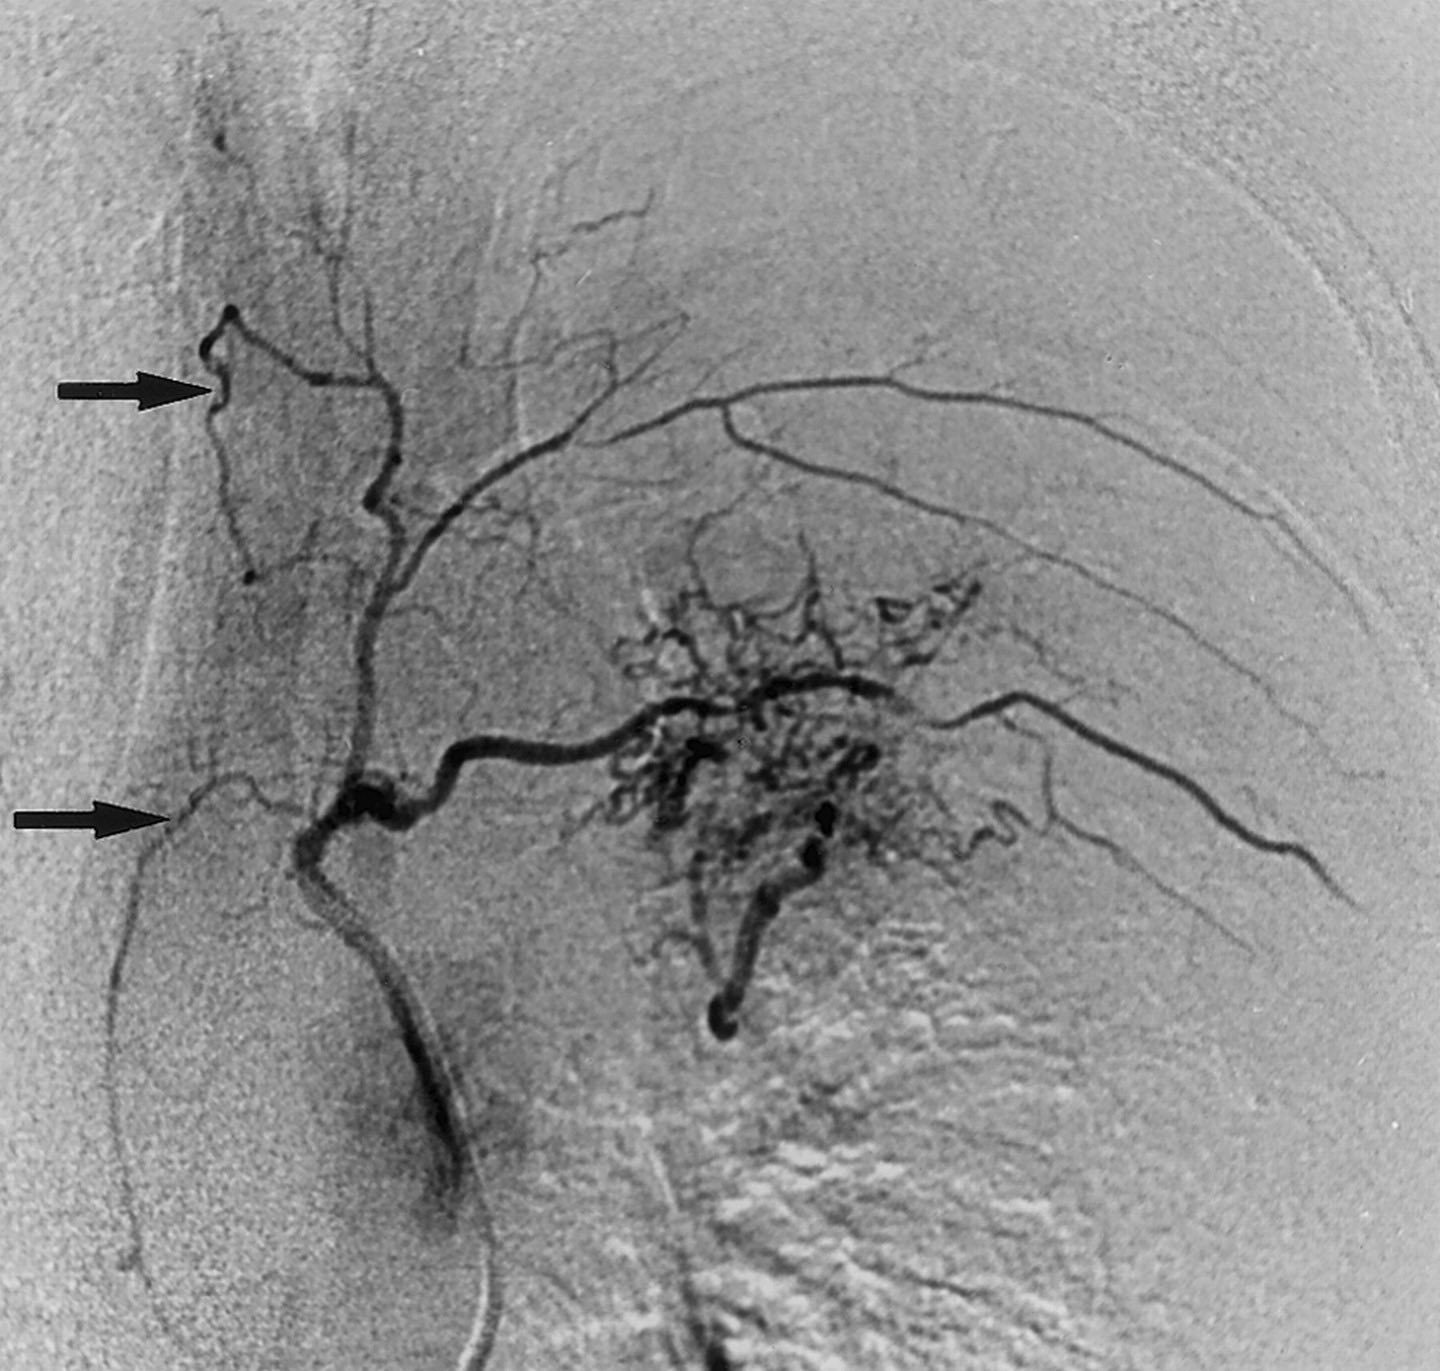

الجوانب التقنيّة للانصمام الشرياني القصبي

يتطلّب الانصمام الشرياني القصبي فهماً دقيقاً للتشريح الوعائي للصدر، مع إدراك التنوّعات التشريحيّة للشرايين القصبيّة وغير القصبيّة. ويُجرى الإجراء عادةً عبر مدخلٍ شريانيٍّ فخذيٍّ ، باستخدام قثطرةٍ انتقائيّةٍ أو فوق انتقائيّة لتقليل خطر الانصمام غير المقصود.

تشمل الموادّ الانصماميّة المستخدمة الجزيئات البوليمريّة، والموادّ المؤقّتة، والملفّات المعدنيّة، والغراء الوعائي، ويعتمد اختيارها على طبيعة المرض، وحجم الأوعية المستهدفة، وخبرة الفريق التدخّلي.